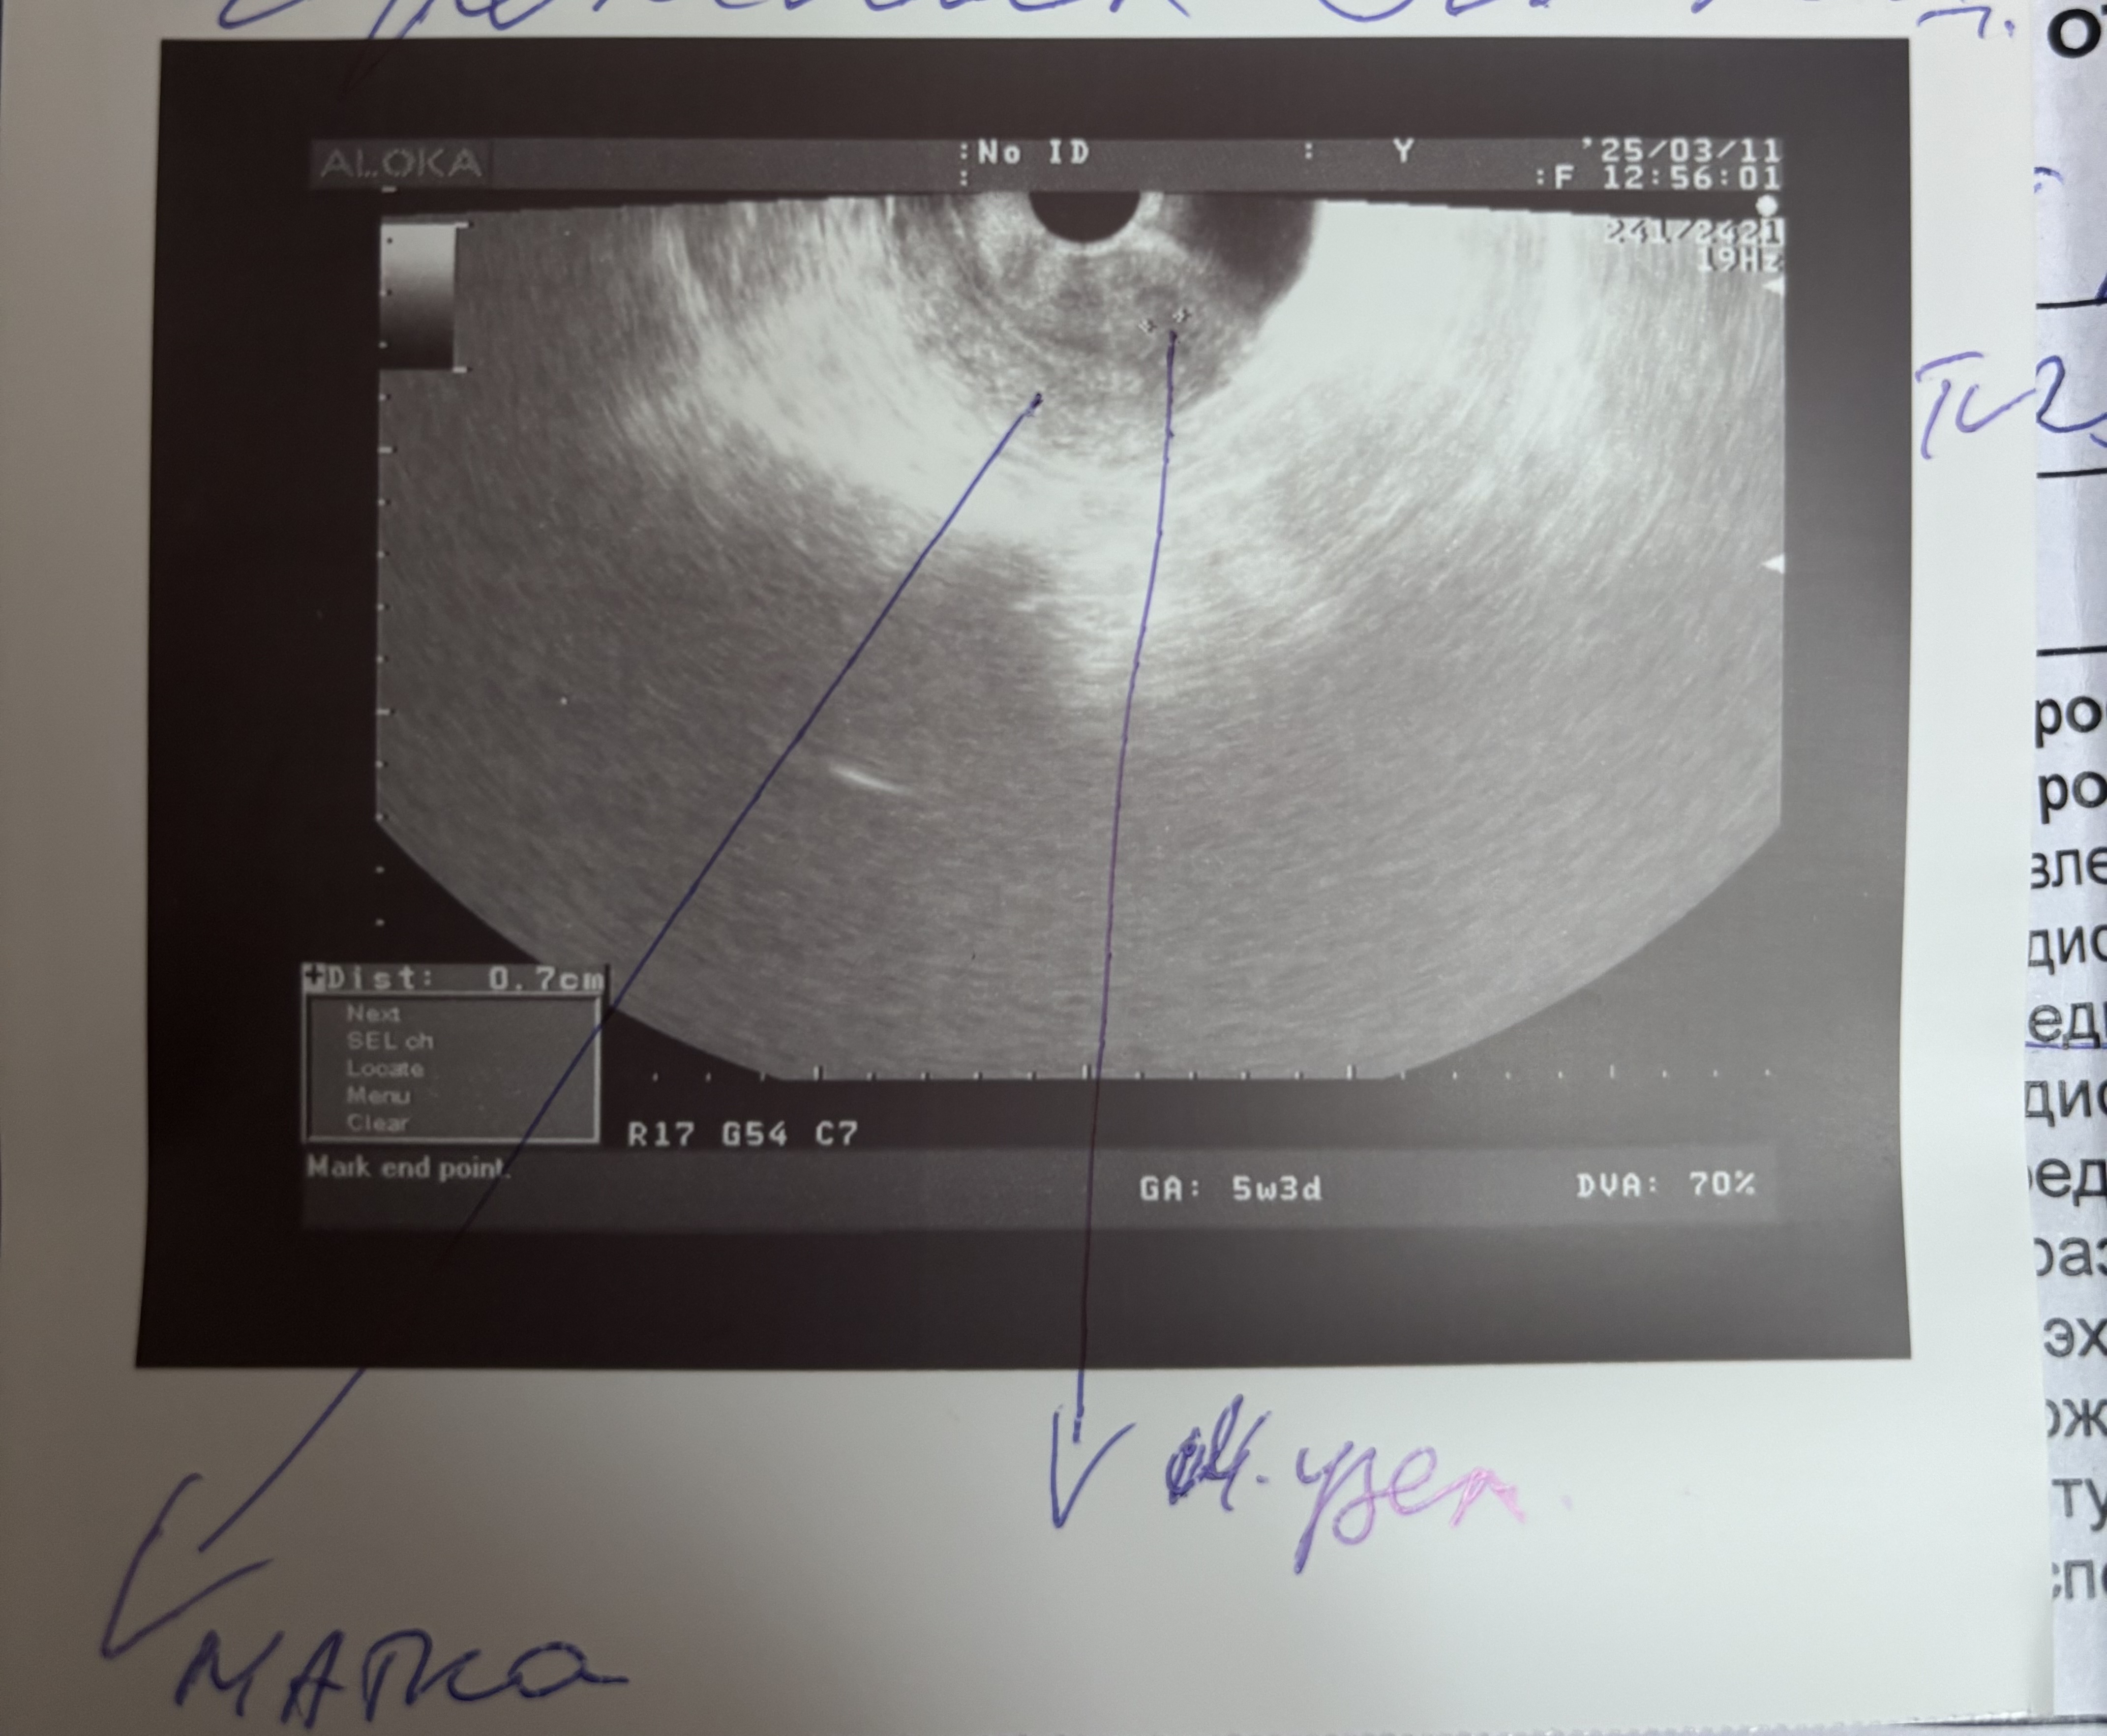

cherry, мне больше интересно есть ли вообще беременность,врач узи полностью ее исключил ,но я перекопала весь интернет и нашла инфу,что это 50/50 Можно увидеть плодное яйцо на 5 неделях уже ,а можно и не увидеть

Аня , что касается узи, вы говорите что у вас 5 недель, но это акушерские недели, судя по тому что у вас только начала появляться вторая полоска на тестах (типа 7 дней задержки), у вас была поздняя овуляция

Аня , к слову, тесты начинают полосатить примерно через 10 дней после зачатия, то есть у вас эмбриональных недель 2 полных от силы